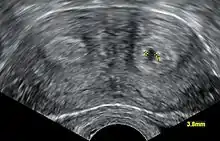

L’examen clinique doit être complété par l’échographie, et selon les cas l’hystérosalpingographie, l’UIV, l’hystéro scopie et la cœlioscopie.

L'échographie utérine est utile à la recherche des causes utérines car celles-ci sont fréquentes et parfois curables. L'échographie, quand elle est orientée, est très performante pour établir un diagnostic différentiel entre utérus cloisonné et bicorne même si l'hystérographie reste la référence dans beaucoup d'autres situations (unicorne, béance, hypoplasie, DES syndrome).